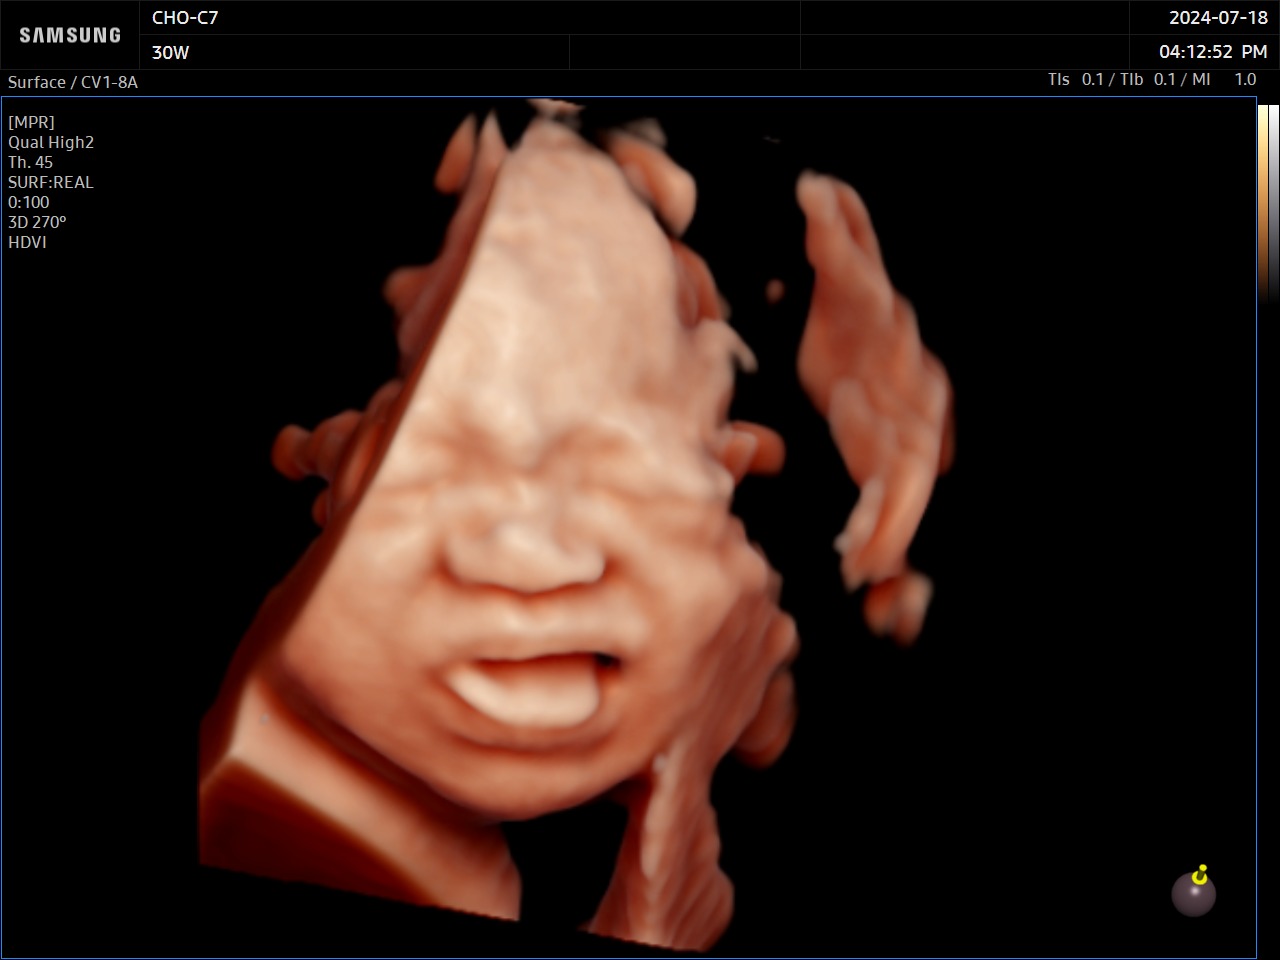

RealisticVue™ affiche une anatomie 3D haute résolution et une perception réaliste de la profondeur. Une source lumineuse est modélisée afin de permettre un effet d’ombre sur les structures et de surligner les zones d’intérêt.